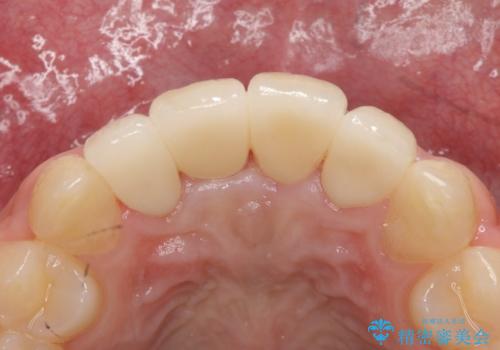

虫歯もしっかり除去して、適合の良い補綴物を装着しました。